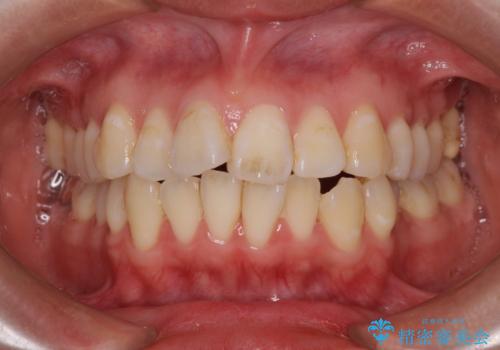

- 歯のデコボコ|口ボコ|八重歯が気になる!|ワイヤー矯正

- 急速拡大装置 狭い骨幅を拡大した上で、口元の突出感を改善する抜歯矯正治療

- 【モニター】とがった口元を抜歯して改善 ワイヤー装置の矯正治療- 担当医 藤巻太一朗

- 出っ歯を治したい ワイヤー装置での抜歯矯正- 担当医 藤巻太一朗